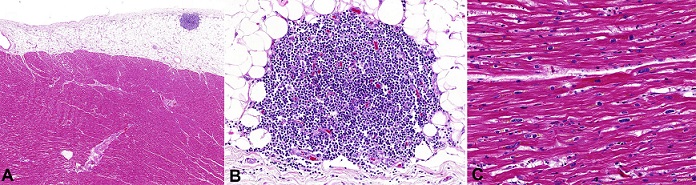

The heart weighted 260.0 g (mRV: 260 g); the coronary arteries were tortuous and obstructions did not exceed 40%; mild/moderate calcification of the aortic valve was observed. Microscopically, cardiomyocyte hypertrophy and rounded foci of small lymphocytes in the epicardial fat layer compatible with CLL infiltration ( Figure 4) were observed.